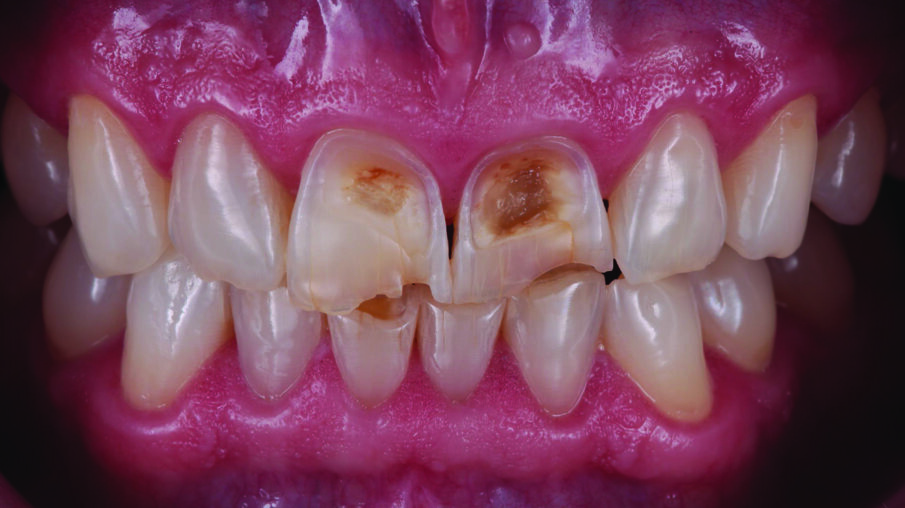

INITIAL SITUATION: Preoperative frontal view of the patient’s teeth, showing severe erosive tooth wear on the vestibular surfaces and incisal edges.